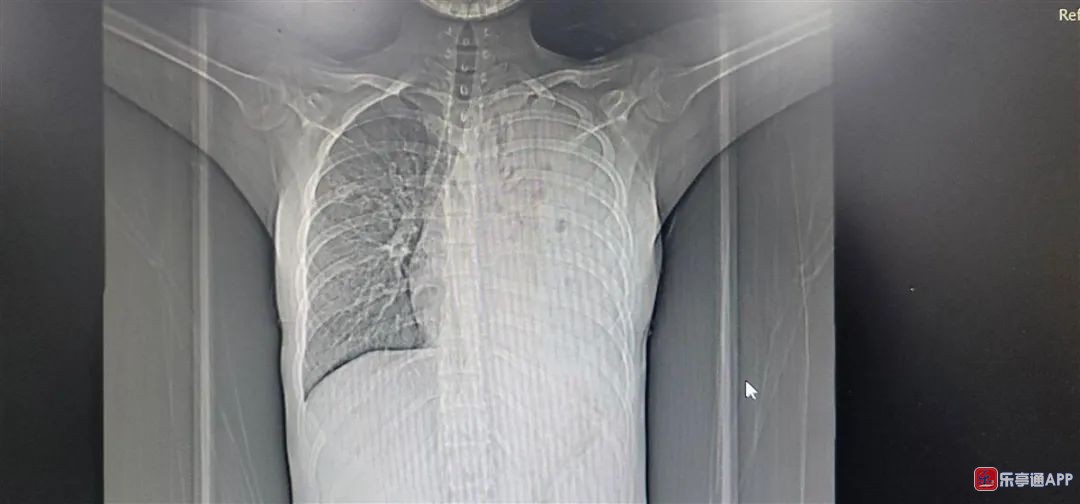

CT影像中,左肺已经消失(右侧是左肺,CT影像是镜像)

医生根据各项检查结果,综合判断,小丽感染了结核病。再一查,她的父母也感染了结核病,好在情况没有小丽严重。

治疗了3个月,医生发现,小丽的左肺依旧没有出现在CT影像中,最终确认,小丽的左肺靠药物治疗已经无法恢复了,要消灭结核菌,治愈疾病,需要对左肺也就是“菌巢”进行手术处理。

经过5个多小时的手术,医生才艰难地将石头一样的左肺从胸腔壁上剔下,并厘清、剪除了它与主气管、血管之间的纠缠,最终清理出胸腔。小丽也成为在该院接受全肺切除的最小患者。

医生介绍,结核菌侵蚀左肺后,产生炎症粘连,让左肺支气管逐渐狭窄、闭塞,造成气体无法交换,痰液无法排除,导致病情快速发展。此时,又加上小丽拖着没有规范治疗,让病菌进一步繁殖,病情进一步恶化,最终让左肺实变,并从CT影像中消失。这一病例,实在令人扼腕叹息。